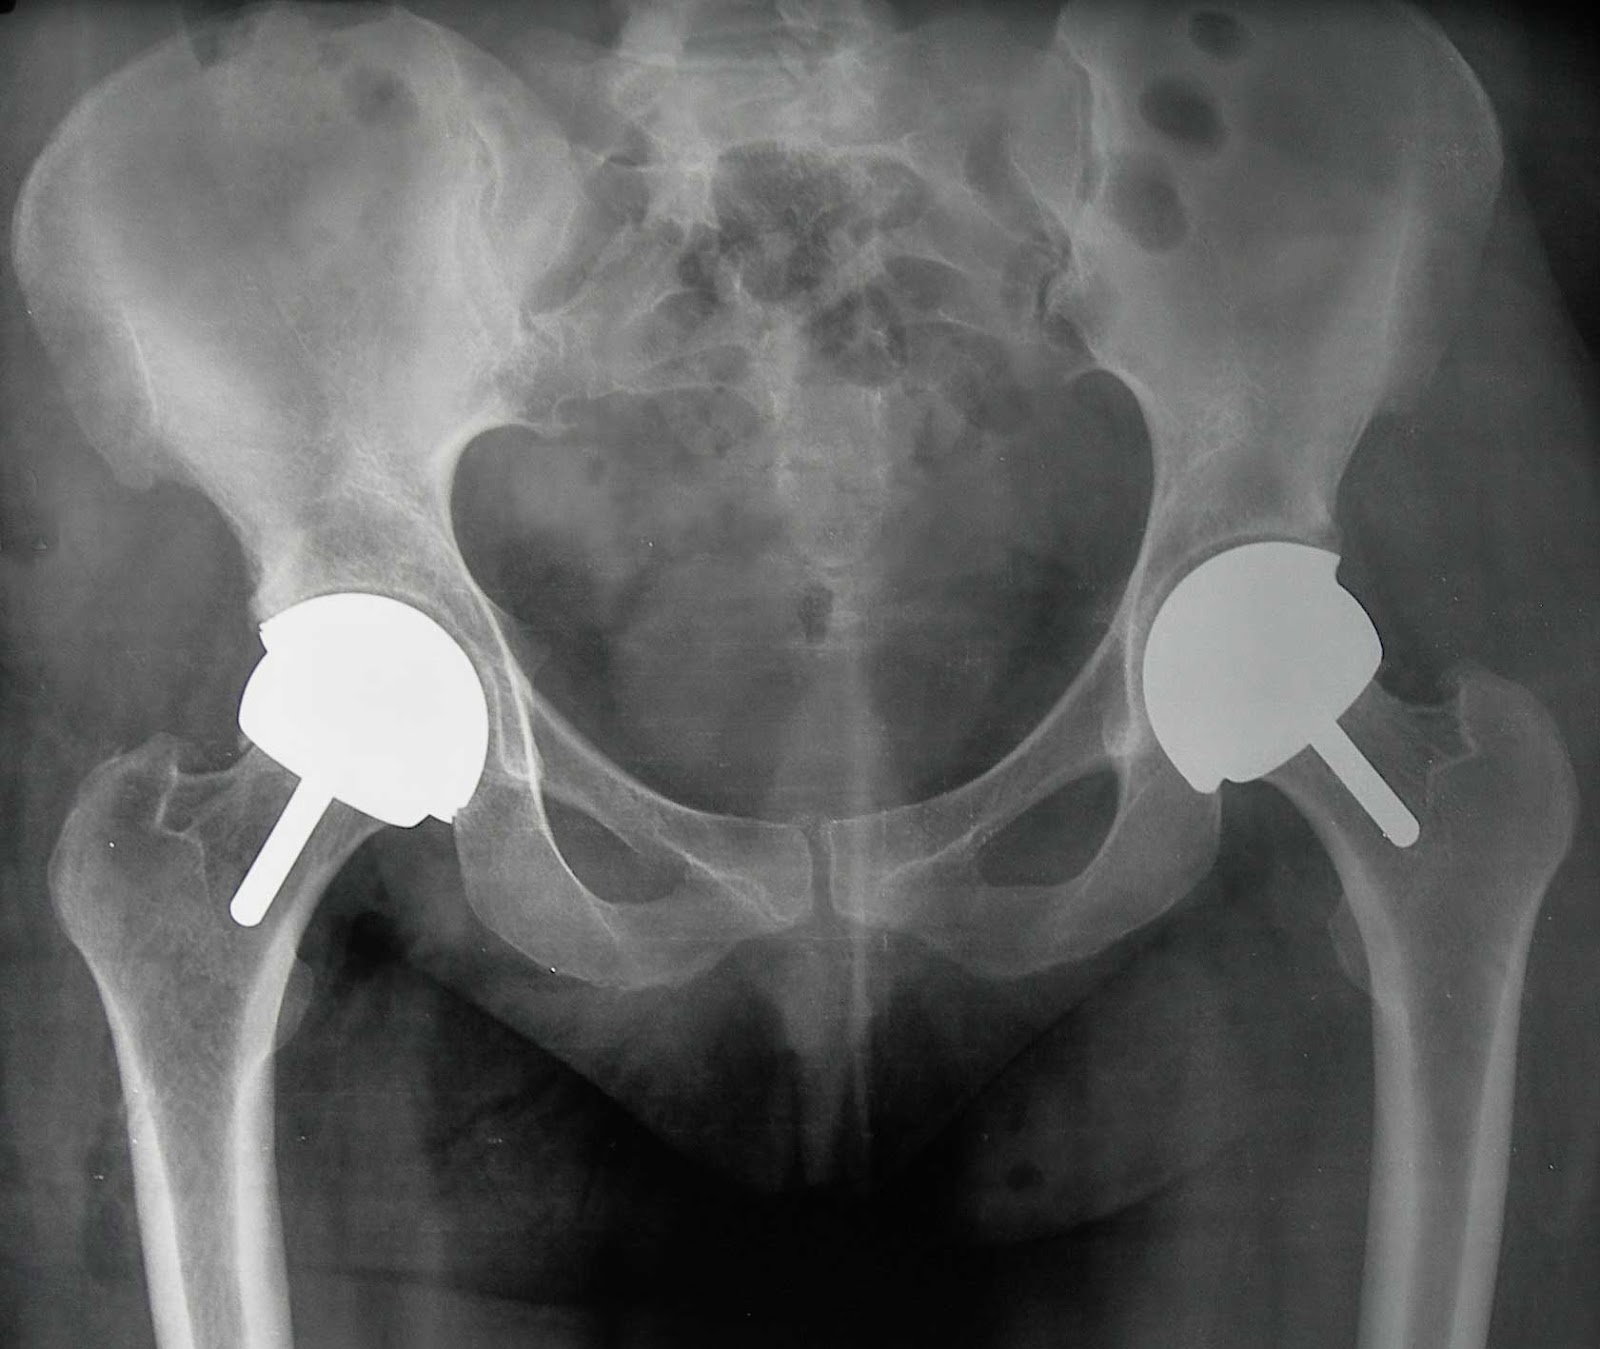

Guide Physical Therapy Guide to Total Hip Replacement (Arthroplasty

Is Hip Replacement Easier Than Knee Replacement . An experienced surgeon could probably do a hip. Recovery time varies for each patient, but most patients are close to fully recovered after. Definition and causes hip replacement surgery, often considered a lifesaver for those. Which is easier to perform, a hip or knee replacement? Hip and knee replacements are fairly common in the u.s. The pros and cons of hip replacement surgery. Therefore, it’s a fairly straightforward process to create and implant parts to replace that joint effectively. Chris pelt, md, is a joint replacement specialist. While knee and hip replacements can help alleviate pain and improve function, there are some differences between the two procedures. So let’s take an honest look at hip, knee, and shoulder replacement surgeries, when you should get them, and the pros and cons of each. People who have dementia or other cognitive decline usually. Recovery time for hip replacement is typically much quicker than knee replacement. Hip replacement surgery is a slightly more straightforward procedure than knee replacement. The most common reason for a hip replacement is osteoarthritis, which involves the deterioration of joint cartilage.